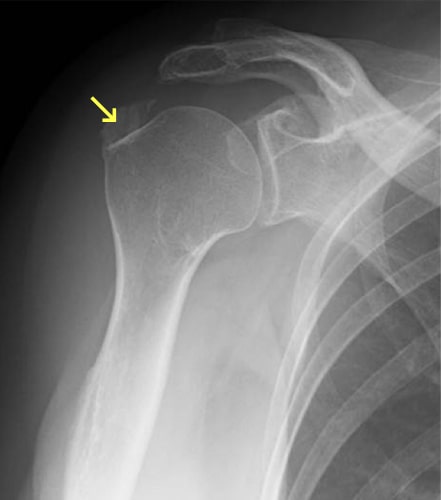

石灰沈着性腱板炎

石灰沈着性腱板炎とは、回旋筋腱板に石灰が沈着することで発症します。石灰が沈着すると急性の炎症を起こし、強い痛みのため著明に関節の動きも制限されます。レントゲンでは上腕骨頭の周囲に石灰の沈着が見られます。自然回復することもありますが、痛みも強く、改善するまでに比較的時間がかかるため、エコー下に石灰を吸引、ステロイド剤を注入することもあります。肩関節の可動域制限がある場合に理学療法を行います。